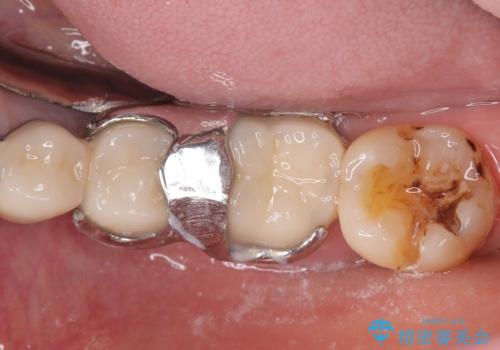

メタルインレー脱離後の窩洞をセラミックインレー窩洞に再形成し直し印象しています。遠心・舌側面のカリエスの除去、残存歯質の破折リスクを考えアンレー形態となりました。

アンレー装着時にはラバーダム防湿を行っています。